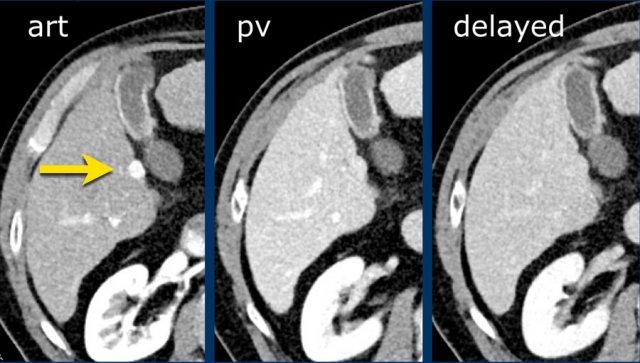

Đây là hình ảnh thì động mạch muộn của một bệnh nhân xơ gan.

Ghi nhận một tổn thương có tăng ngấm thuốc không dạng viền (mũi tên vàng).

Ở thì muộn, tổn thương có hiện tượng washout.

Đây là những đặc điểm điển hình của HCC.